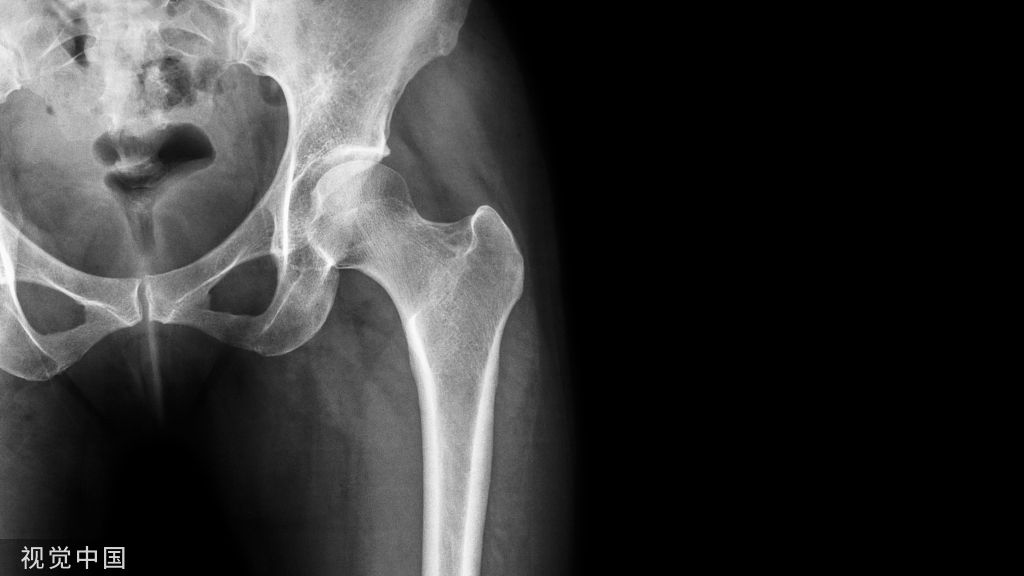

带锁髓内钉的应用扩大了髓内钉的手术指征,目前使用最多的是各种扩髓带锁髓内钉系统,主要用于髋部骨折(股骨转子间、转子下骨折)、股骨于骨折、股骨远端骨折、胫骨干骨折、肱骨骨折(外科颈骨折、肱骨干骨折)。

1. Gamma 钉

Gamma 钉适用于股骨颈基底至小转子水平以上的各种类型的骨折。Gamma 钉内固定技术除感染外无绝对禁忌证,伴有严重骨质疏松患者术后的早期活动需要一定的限制。

4. 股骨近端髓内钉

股骨近端髓内钉系统( proximal femoral nail system,PFN)是由AO内固定学会根据 Gamma钉原理改良设计而研制的用于股骨近端骨折治疗的髓内固定材料。PFN 适用于股骨颈基底至小转子以下 5cm 的骨折,也就是 AO 分类中 31-A的所有骨折和转子高位股骨干骨折。